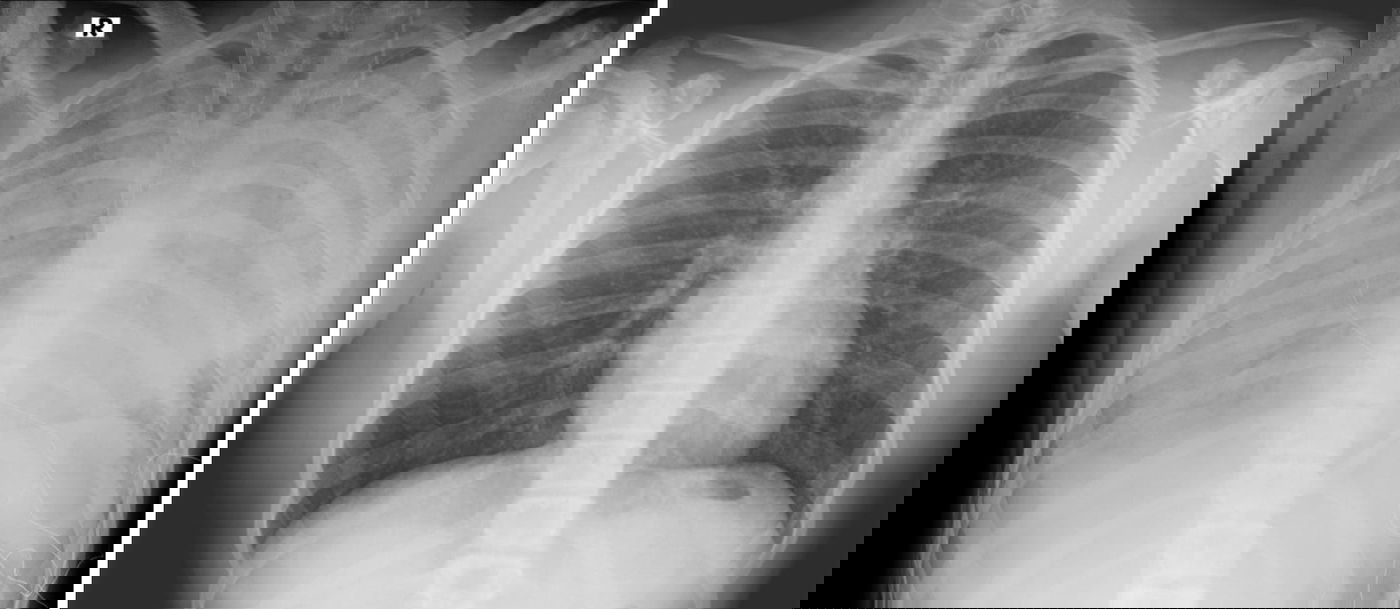

הנער הועבר למרכז שניידר מבית החולים קפלן, במצב של קריסת ריאות. מבירור רפואי מקיף שערכו בבית החולים קפלן עלה כי מצבו של הנער נגרם, ככל הנראה, כתוצאה מעישון של סיגריות אלקטרוניות. הנער נמצא כעת ביחידה לטיפול נמרץ לב שהוא בהכרה, אך כאמור מחובר לאקמו.

פרופ' עובדי דגן, מנהל היחידה לטיפול נמרץ לב מסביר על המקרה: "הנער התקבל ליחידה לטיפול נמרץ לב במצב קשה מאד כשריאותיו אינן מתפקדות, והוא זקוק לתמיכה מלאה של מכשיר אקמו. אנו מטפלים בו ומקווים מאד לשיפור במצבו בימים הקרובים. הנזק שנגרם, ככל הנראה, מעישון של הסיגריות האלקטרוניות הוא נזק עצום. אנו קוראים לכל ההורים, מנעו את המקרה הבא".

ד"ר חבצלת ירדן בילבסקי, מומחית בפרמקולוגיה קלינית וטוקסיקולוגיה בבית החולים מסבירה: "סיגריות אלקטרוניות עלולות לגרום נזק חמור אף יותר מסיגריות רגילות. בספרות הרפואית קיימים דיווחים רבים על מחלת ריאות משנית לשימוש יתר בסיגריות אלקטרוניות, עד כדי קריסת הריאות".